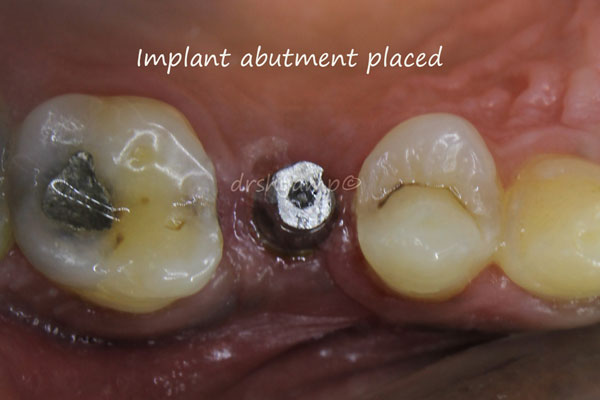

immediate dental implant

immediate dental implant

immediate dental implant

immediate dental implant

immediate dental implant

immediate dental implant

immediate dental implant

immediate dental implant

immediate dental implant